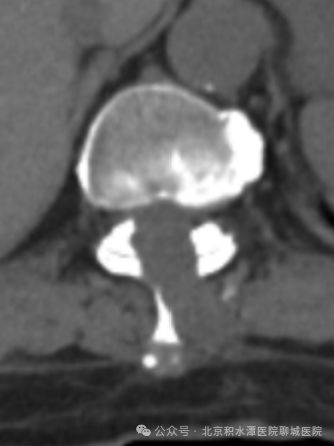

术前影像:T11/12胸椎黄韧带骨化,胸椎椎管狭窄

术后影像:去除少量骨质扩大胸椎椎管

并取出骨化的黄韧带